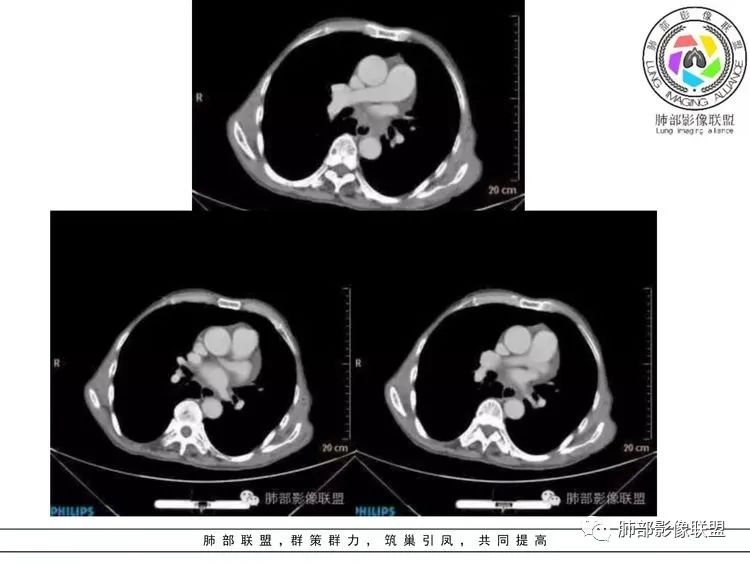

放射小白:老年男性,右侧肺门可见团块状占位包绕气管,气管受压变窄,纵隔见巨大团块状占位,另纵隔可见肿大淋巴结,增强肺门及纵隔肿块强化不明显,内部可见血管影,周围结构只是受压移位,另颌下淋巴结穿刺慢性淋巴结炎,首先考虑小细胞癌,鉴别淋巴瘤、结节病。

宇宙:右肺下叶小结节,右肺门及中后纵膈淋巴结肿大融合,强化均匀,主支气管、中间段及下叶支气管受压变窄,右下肺静脉受压变窄,考虑小细胞癌,鉴别淋巴瘤

丽:老年男性,纵隔及肺门多发肿大淋巴结,相互融合呈团块状,包绕支气管官腔,呈针尖样狭窄,增强后轻度强化,考虑小细胞肺癌

放射线:纵隔及肺门淋巴结肿大相互融合呈冰冻纵膈,支气管受压变窄呈针孔样,老年男性吸烟患者,考虑小细胞肺癌。

采莲:老年男性,有吸烟史,双颈部肿块,双肺纵隔淋巴结多发淋巴结肿大并融合成块,气管及右肺下叶支气管受压狭窄,考虑恶性,淋巴瘤可能,鉴别小细胞肺癌。

崔少钢:老年男性,有吸烟史,右肺下叶背段示小结节,纵隔、腋窝及右肺门淋巴结节肿大,气管受压狭窄,后纵隔软组织内示血管走行,考虑小细胞>淋巴瘤。

我只是邓较瘦:晨读老年男性,长期吸烟。右肺门、纵隔多发肿大淋巴结、融合成团块,中间支气管、右肺下叶支气管受压变窄,增强扫描强化程度较轻,血管包埋。另两侧腋窝亦见多发肿大淋巴结。常规恶性没问题,小细胞?淋巴瘤?但是於老师的病例总感觉没那么简单。

谢加平:纵隔内中后纵隔及右肺门淋巴结肿大,形成大肿块,整体密度均匀,并轻度强化,见“血管飘浮”征,包绕气管分叉及右主支气管及中间段支气管明显受压狭窄,并包埋右肺门血管束,无侵蚀破坏,右肺动脉后壁见压迹影,右肺下叶背段有阻塞性炎症,首选淋巴瘤,支气管超声内镜活检,明确诊断!